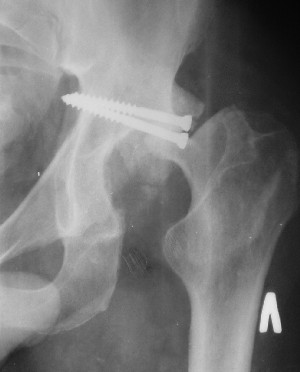

Послеоперационный снимок прямой 5/05/03

|

Больной 18 мая 2003 года в автоаварии получил перелом левой вертлужной впадины, вывих бедра. Госпитализирован в один из стационаров области.Вывих вправлен. В последствии бедро вывихивалось еще дважды. На консультацию был представлен снимок от 19.05.03г., больной переведен к нам 3.06.03г. Снимок при поступлении - перелом впадины, задне-верхний вывих бедра. 05.06.2003 г. выполнено открытое вправление вывиха левого бедра и остеосинтез стенки вертлужной впадины двумя винтами. Послеоперационный период без осложнений. Объем движений в левом тазобедренном суставе восстановился полностью. Выписан на амбулаторное лечение в удовлетворительном состоянии с рекомендациями 3 месяца ходить на костылях без нагрузки на оперированную конечность. На контрольных рентгенограммах левого тазобедренного сустава 13.10.2003 г. - признаки консолидации перелома; плотность, форма головки и состояние суставных поверхностей удовлетворительные. Разрешена дозированная осевая нагрузка, на конечность с использованием дополнительной опоры. 19.12.2003 г. больной обратился с жалобами на боли в левом тазобедренном суставе. На рентгенограммах левого тазобедренного сустава 19.12.2003 г., 20.02.04г. - асептичекий некроз головки бедра. 5.04.04г. - эндопротез. Сейчас ходит без трости, не хромает. Особенность эндопротезирования - при удалении винтов прослежена линия перелома заднего края впадины и предложено установить чашку несколько меньшего диаметра, чтобы она была покрыта несломанной частью.